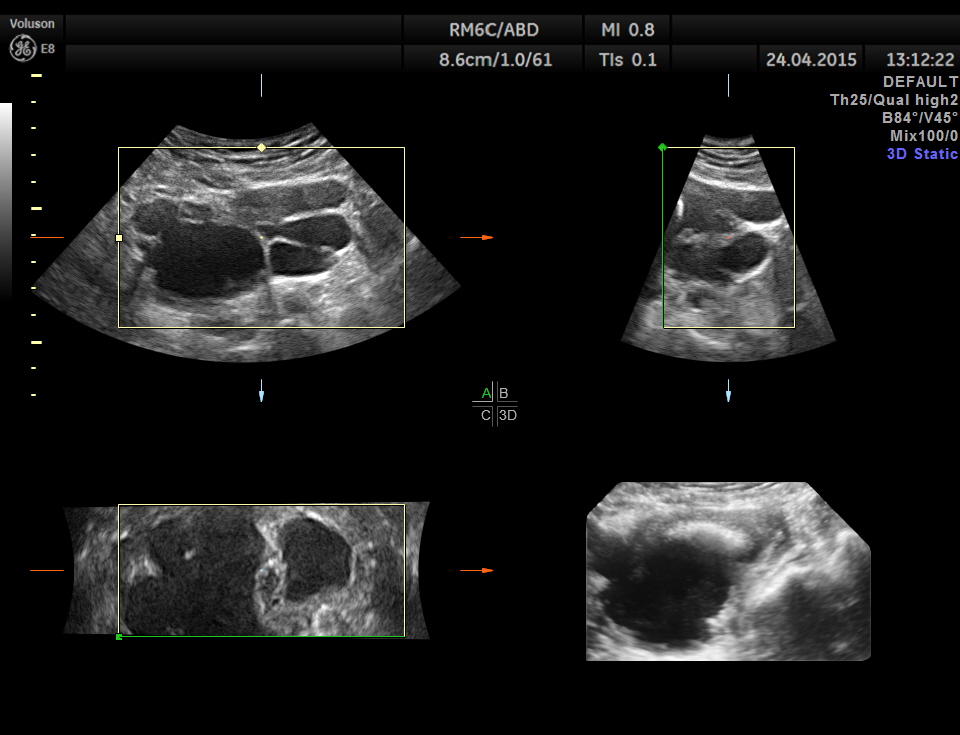

Scan of the urinary bladder in a more cephalic angle shows the following :

Superior angling shows a multi cystic pelvic mass – ? bladder diverticulae